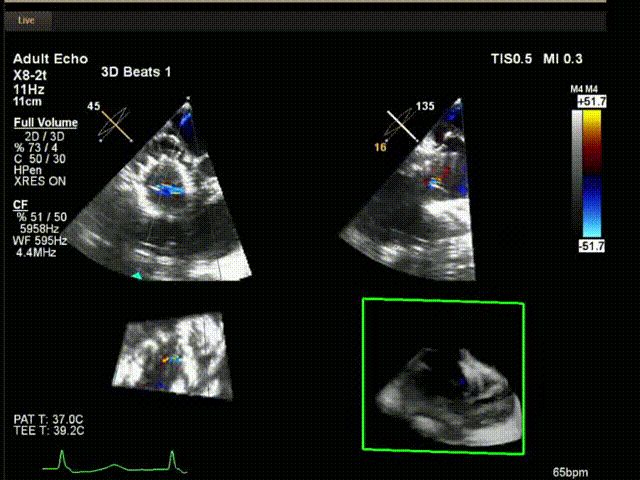

術中超聲

陸方林教授通過遠程線上帶教的方式,與林逸賢教授團隊共同完成了此次LuX-Valve Plus人工瓣膜的首例植入。術后食道超聲提示三尖瓣反流完全消失,無瓣周漏,且LuX-Valve Plus人工瓣膜的兩個夾持鍵成功抓取瓣葉,錨定牢固,人工瓣膜穩定性良好。

手術在全麻狀態下開展,此次手術采用經頸靜脈入路的方式。在TEE及DSA雙重引導下,術者調整輸送器頭端角度使得其與三尖瓣瓣環平面垂直。在輸送器進入右心室后釋放室間隔錨定裝置,而后釋放瓣葉夾持件(2個耳片結構)成垂直狀態。在TEE及DSA確定夾持件固定至三尖瓣葉根部且位于右室側后釋放人工瓣心房側盤片。隨后調整瓣膜同軸性以及室間隔錨定件位置(貼合室間隔),進而釋放室間隔錨定裝置,并再次確認瓣膜位置、穩定性及同軸性,解離人工瓣膜與輸送器間連接,并撤出輸送器,完成了LuX-Valve Plus人工三尖瓣瓣膜的植入。